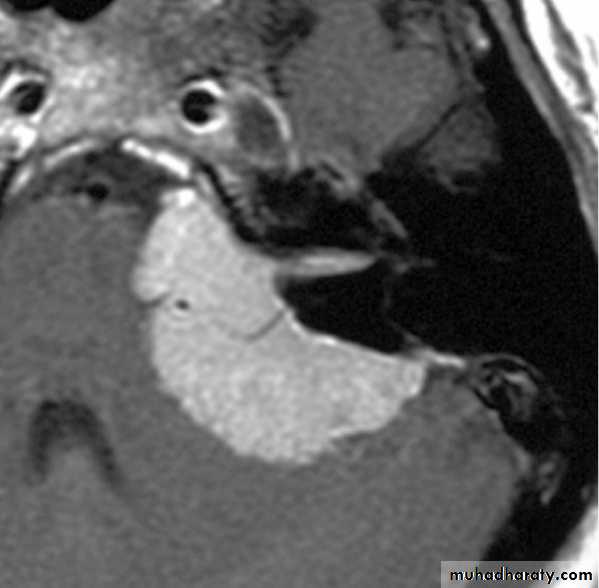

Diagnosis

CT scan &/ or MRI

Four-vessel angiography +EmbolizationIn large tumours, embolization of feeding vessels 1-2 days before operation.

(c) MRI with gadolinium contrast is the gold standard for diagnosis of acoustic neuroma.